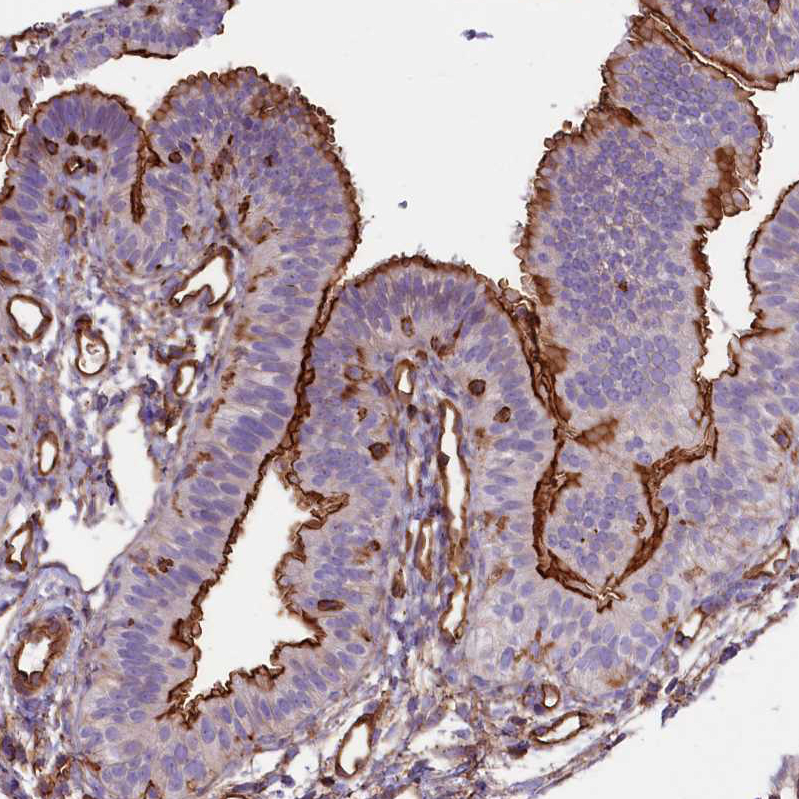

Immunohistochemical staining of human cerebral cortex shows strong membranous positivity in neuropil.